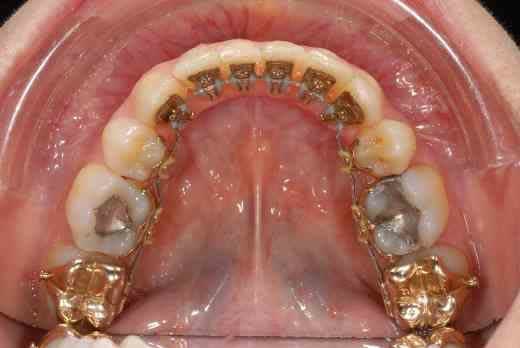

voilà quelques roros et un an plus tard...

elle est merdique hein ma 12, décidément je m'en remets pas de cette 12 :-(((

J’aurais tendance à penser comme val en ce qui concerne ta classe II, mais ce qui me turlupine le plus dans ton cas, Doc, c’est la différence de hauteur des collets des incisives apparue pendant le traitement.

La ligne des collets ne semble pas trop mauvaise sur la photo d’avril, ce n’est malheureusement plus le cas sur celle de décembre, où le collet de la 11 apparaît plus bas que celui de la 12.

Par rapport à ta lèvre supérieure, qu’est-ce que cela donne dans le sourire ?

Comment ton orthodontiste compte-t-elle gérer cela ?